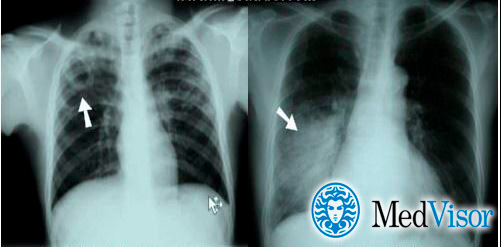

Рентген

Опасным воспалением при туберкулезе или пневмонии считается верхнедолевой очаг поражения, который чаще всего поражается микобактериями.

При пневмонии обнаруживаются на рентгене изменения, позволяющие отличить ее от туберкулеза:

- Уплотнение (инфильтрация) участка легких с неявными, размытыми очертаниями или в виде дымки (характерно для снимков при острой форме).

- Усиление легочного рисунка (при интерстициальной форме).

Флюорографией при пневмонии чаще выявляется поражение нижних и средних частей с изменениями корня легкого.

При туберкулезном инфицировании изменения отмечаются в верхней части легкого, отличаются четкими очертаниями, без видимых изменений корня.

На рентгенограмме обнаруживается при туберкулезе:

- Диссеминированном. Множество мелких, хорошо очерченных, или более крупных пятен, есть каверны.

- Очаговом. Уплотнение находится не ниже 2 ребра, вокруг могут быть фиброзные тяжи, усилен легочный рисунок.

- Инфильтративном. Уплотнения правильной округлой формы на рентгеновском снимке в верхней легочной доле.

- Казеозной пневмонии. Множество полостей распада с неровными краями, очагами отсева, смещением средостения в больную сторону груди.

Отличия пневмонии от туберкулеза на рентгене

При пневмонии на рентгенограмме обычно видны инфильтраты и уплотнения. Типичное изображение представляет собой однородное или неоднородное белое пятно в основании пораженного легкого, либо в средней его трети. Типичным также считается плевральный выпот – скопление жидкости в плевральной полости – на той же стороне, что и очаг пневмонии.

Туберкулез обычно проявляется в виде кавитации (пустоты) в верхней части легкого. На снимке она выглядит как округлая полость. При этом также имеет место плевральный выпот.

Впрочем, отличия пневмонии от туберкулеза могут быть не такими очевидными как на снимке. Иными словами, одна флюорография не является показательной.